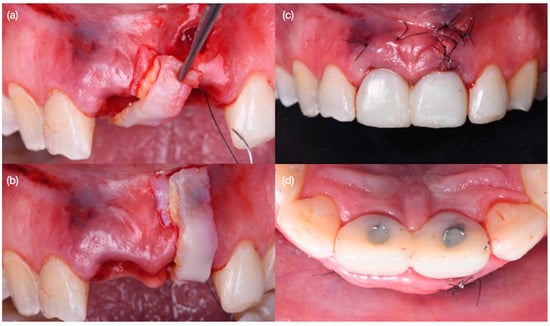

Figure 4. Atraumatic tooth extractions. (a) Crowns removed, (b) extraction of left central incisor, (c) extraction of right central incisor, and (d) both teeth extracted.

Diagnostic three-dimensional digital scans (iTero Lumina, San Jose, CA, USA) of the maxilla and mandible were taken, and a traditional facebow record (Artex Facebow, Amann Girrbach, Koblach, Austria) was obtained. Printed models (Phrozen Sonic Mini 8K Resin 3D Printer, Phrozen Technology, Hsinchu City, Taiwan) were then fabricated and mounted on a semi-adjustable articulator (Artex CR, Amann Girrbach, Koblach, Austria). A diagnostic wax-up was performed and mounted in the articulator. The patient also received an intra-oral mock-up with a putty index guide (Elite P&P, Zhermack, Badia Polesine, Italy). An initial CBCT scan and the intra-oral scan were used to digitally plan the implant placement (Exocad DentalCAD, Darmstadt, Germany) and print the surgical guide (Phrozen Sonic Mini 8K Resin 3D Printer, Phrozen Technology, Hsinchu City, Taiwan) (Figure 3). Atraumatic tooth extractions were performed for both maxillary central incisors with the use of a periotome (Anterior Straight PT6, Hu-Friedy, Chicago, IL, USA) and forceps (Upper Anterior Atlas FAF1IS, Hu-Friedy, Chicago, IL, USA), only providing vertical forces, and avoiding any horizontal force (Figure 4). The extraction sockets were cleaned thoroughly with curettes (Universal Curette, Hu-Friedy, Chicago, IL, USA), and the abscess cavity was irrigated with saline solution and chlorohexidine to flush out all the debris and blood. The 3D-printed surgical guide was placed in position, osteotomies were performed, and two implants (3.5 mm diameter; 11.50 mm length, Helix GM, Neodent, Basel, Switzerland) were placed at the planned depth (Figure 5 and Figure 6). An autogenous soft tissue graft was harvested from the palate and positioned on the facial surface of the maxillary left side implant using polyethylene sutures. Interim abutments (Gm Temporary Abutments for Crown, Neodent, Basel, Switzerland) were placed with screw-retained non-occluding interim crowns (Figure 7). The patient had regular follow-up evaluations at 2, 4, 7, and 10 weeks, and at 3 and 4 months, after the implant placement. The provisional restoration was recontoured at week 10, and new sets of interim restorations were made at 3 and 4 months (Figure 8). The patient and clinicians were fully satisfied with the contour obtained with the last set of provisional restorations at 4 months, and it was decided to continue the final stage of the treatment (Figure 9).